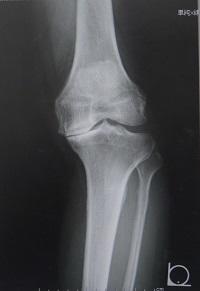

膝関節は外側区画と内側区画の2区画に分かれます。

変形や軟骨の摩耗が、外側区画か内側区画のどちらかに限局している症例(左)においても、従来は内側区画と外側区画の両方を人工関節に置き換える全置換術(右)が施行されていました。